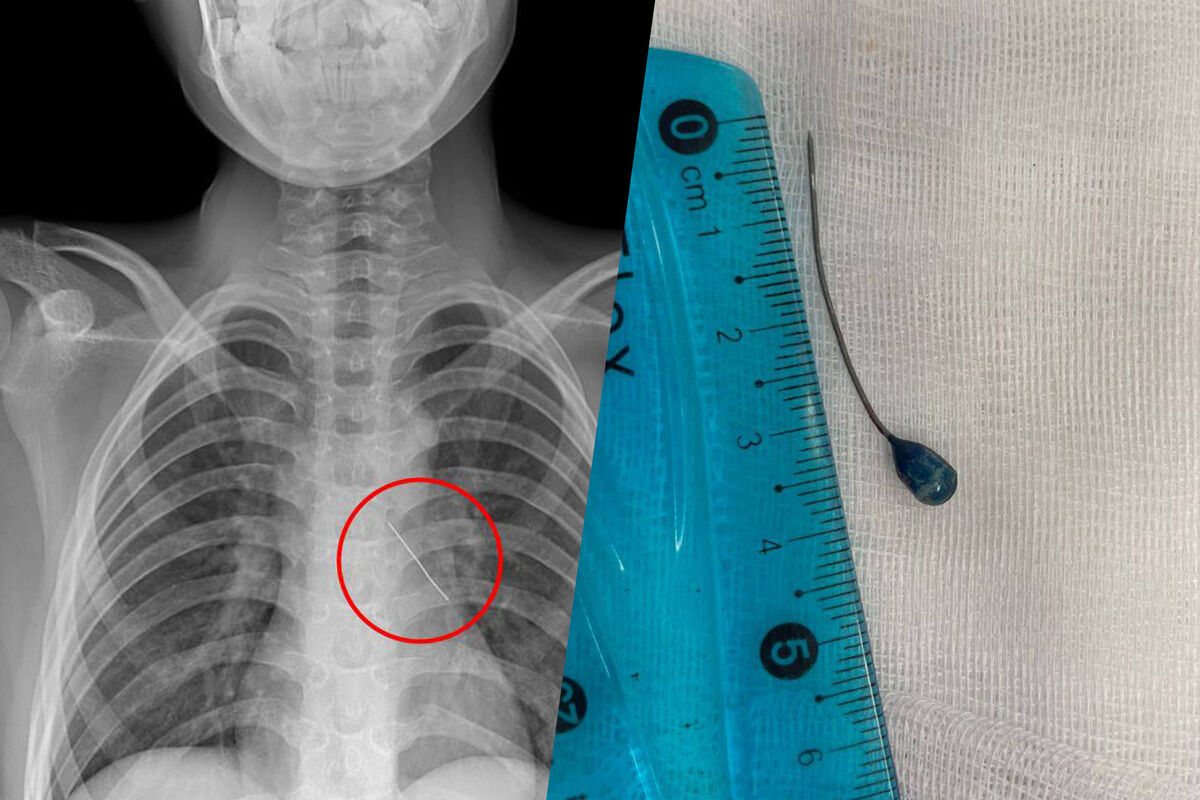

При поступлении в больницу подросток мог говорить только шепотом и жаловался на сильные боли в груди. Рентген показал, что инородное тело находится в области нижней доли левого бронха. Вокруг булавки скопилась мокрота, а острый конец пронзил стенку бронха — это могло привести к коллапсу легкого.

Врачи отделения реконструктивной хирургии провели малоинвазивную операцию. Через эндоскоп они удалили скопления слизи, обнаружили колпачок французской булавки и с помощью оптических щипцов аккуратно извлекли инородное тело. Кровотечение было минимальным и остановилось самостоятельно. Через три дня мальчика выписали под наблюдение врачей по месту жительства.